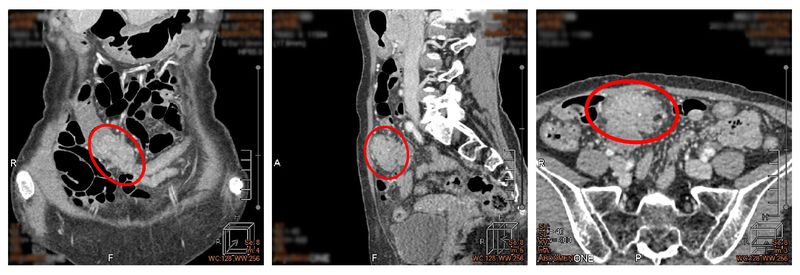

62歲王女士,無家族病史,不煙不酒、飲食清淡,平日也很注意健康,曾於五年前門診發現1顆2mm及1顆5mm的瘜肉,但未進行追蹤檢查,加上新冠疫情考量也遲未就醫。今年5月開始,王小姐下腹持續有鼓脹感,直到8月初安排健康檢查,結果在橫結腸發現異常腫塊,並已造成腸腔環狀狹窄,內視鏡無法插入狹窄後方,後經切片診斷為大腸癌,目前已安排治療中。

▲在橫結腸發現異常腫塊,經切片診斷為大腸癌